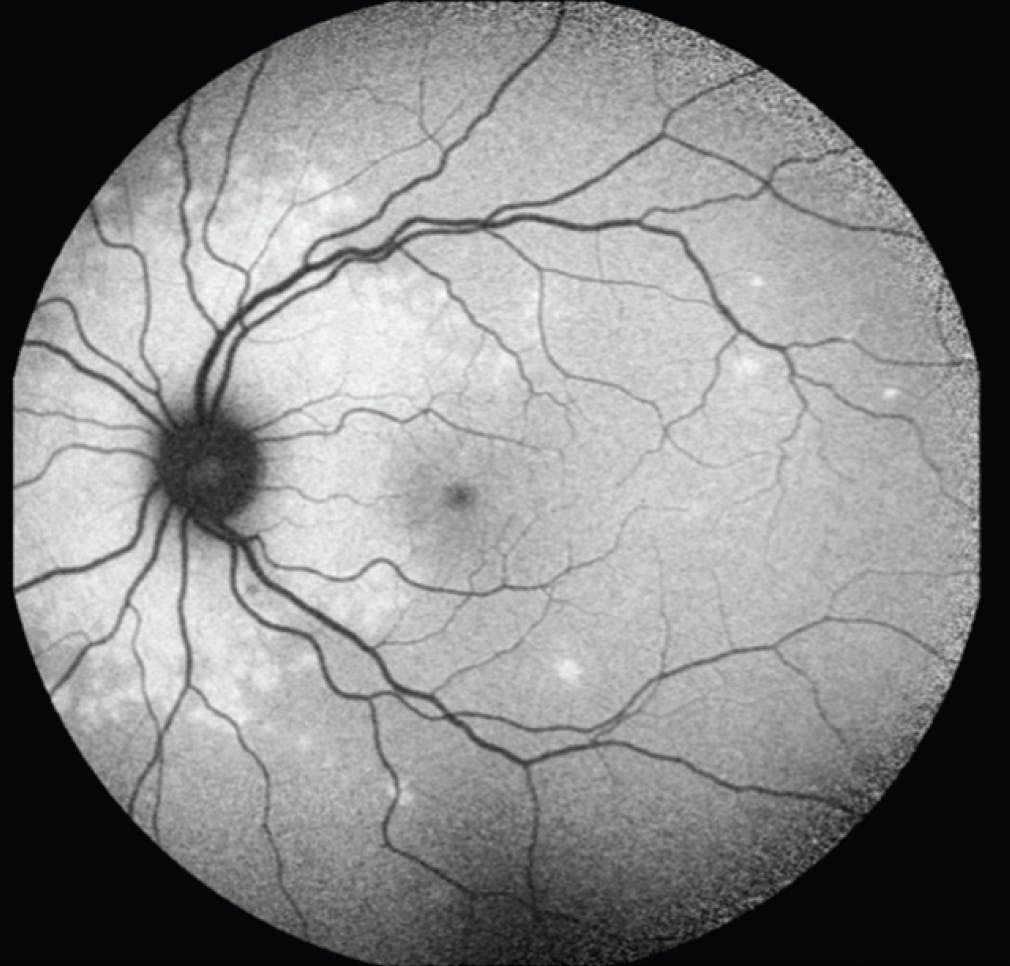

On examination, VA was 20/20 OU. There was no afferent pupillary defect, and IOP and visual fields were within normal limits in each eye. Anterior segment examination was unremarkable; notably, there was no anterior chamber inflammation in either eye. Fundoscopic examination revealed subtle deep, yellow lesions in the peripapillary retina of the left eye. OCT demonstrated attenuation of the ellipsoid and interdigitation zones in the nasal macula (Figure 1). Fundus autofluorescence (FAF) revealed a wreath-like configuration of hyperfluorescence around the optic nerve with numerous noncontiguous, smaller areas of hyperfluorescence throughout the macula and midperipheral retina (Figure 2). FA also demonstrated a confluent area of hyperfluorescence centered around the optic nerve, which increased in intensity in the later frames, consistent with staining (Figure 3).

<p>Figure 2. On initial presentation, the left eye demonstrates a ring of circumpapillary hyperautofluorescence and surrounding, scattered smaller foci of hyperautofluorescence on FAF.</p>

Figure 2. On initial presentation, the left eye demonstrates a ring of circumpapillary hyperautofluorescence and surrounding, scattered smaller foci of hyperautofluorescence on FAF.